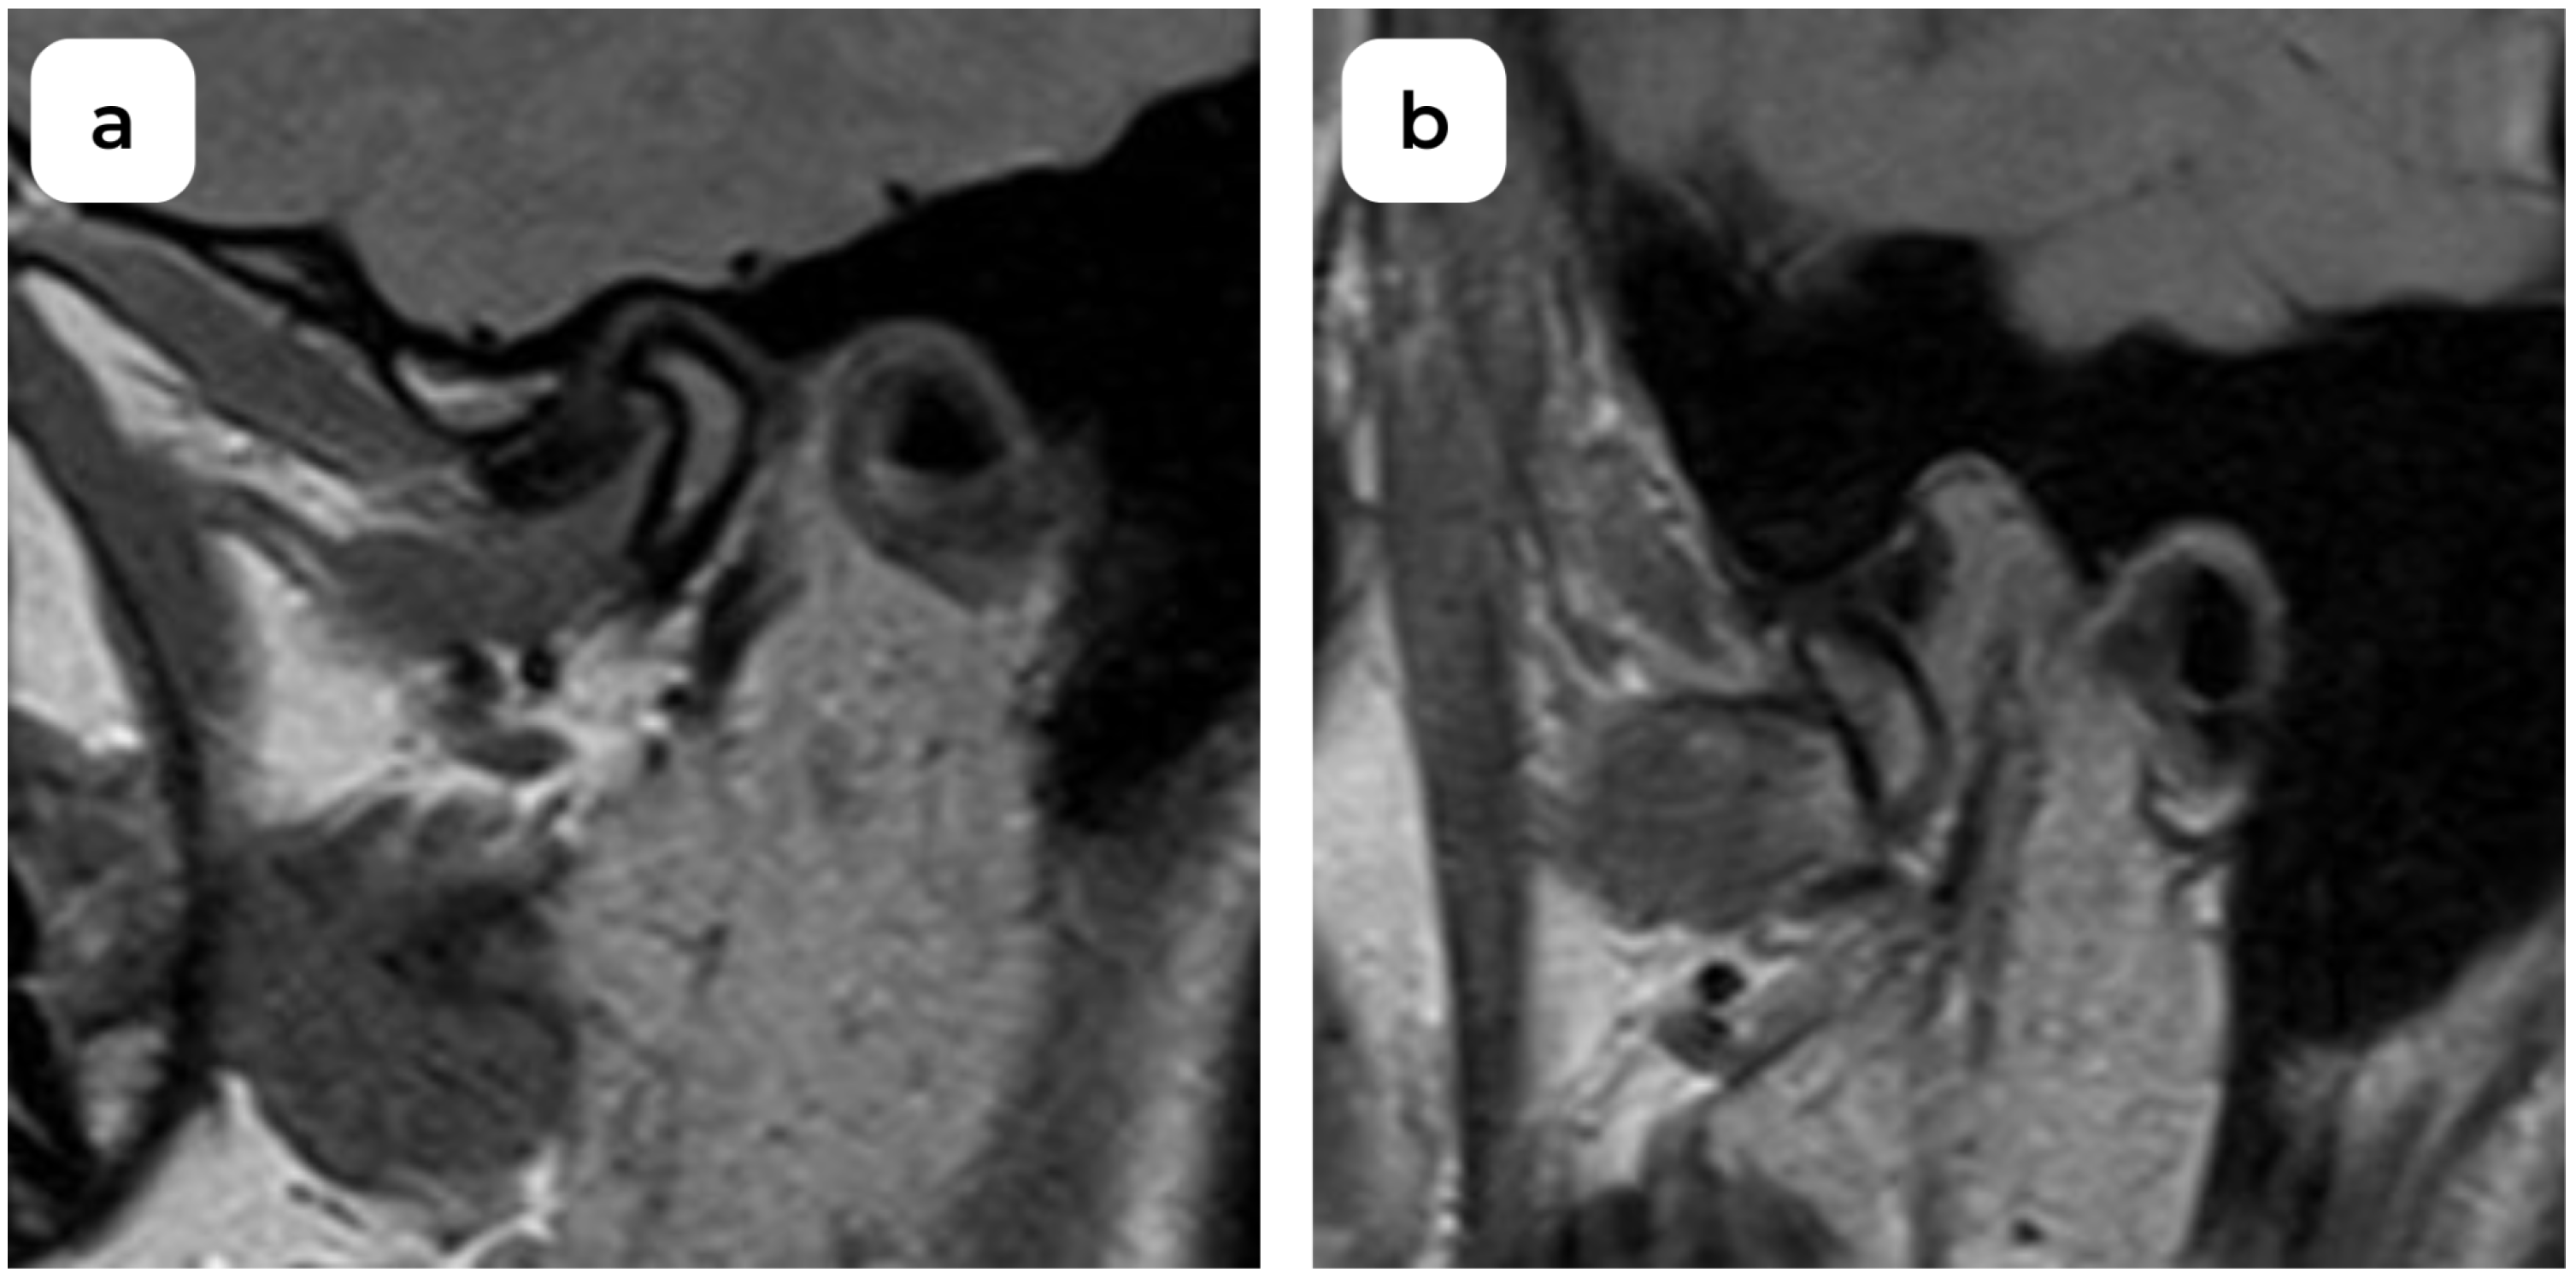

An Examination of Temporomandibular Joint Disc Displacement through Magnetic Resonance Imaging by Integrating Artificial Intelligence: Preliminary Findings